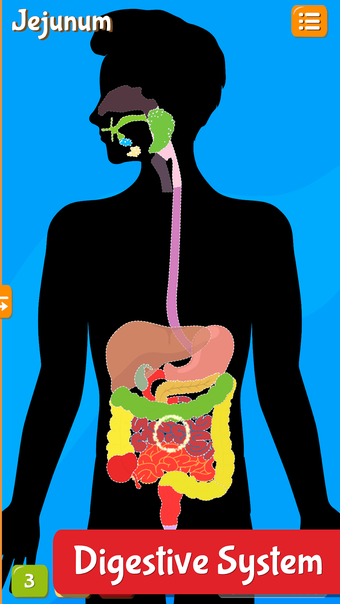

Anatomix es un juego de aprendizaje de anatomía humana que te enseñará a identificar todos los huesos del cuerpo humano y te permitirá explorar cada sistema en detalle. A medida que explores cada sistema, podrás identificar todos los huesos, músculos y otras estructuras.

Además de eso, podrás utilizar los diferentes huesos para identificar los diferentes sistemas.

La aplicación también te ayudará a identificar los diferentes huesos de tu propio cuerpo y te permitirá explorar cada sistema en detalle.